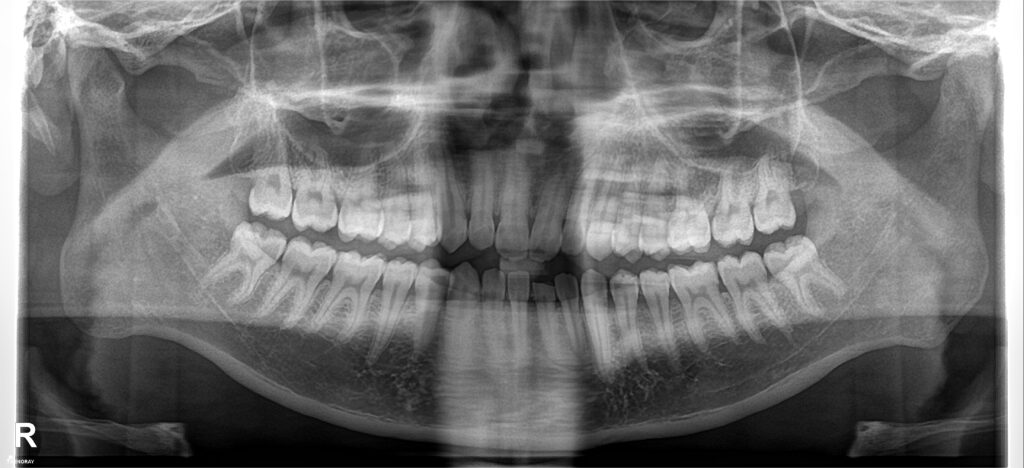

Cũng là khớp cắn ngược nhưng xét về độ khó thì khớp cắn ngược do răng điều trị sẽ đỡ vất vả hơn cắn ngược do xương nhiều. Bệnh nhân nam sinh năm 1998 đến khám niềng với mong muốn cải thiện nụ cười móm.

Kết quả tháo niềng sau 1.5 năm, thay đổi tích cực trên cả lâm sàng và trên phim xquang.